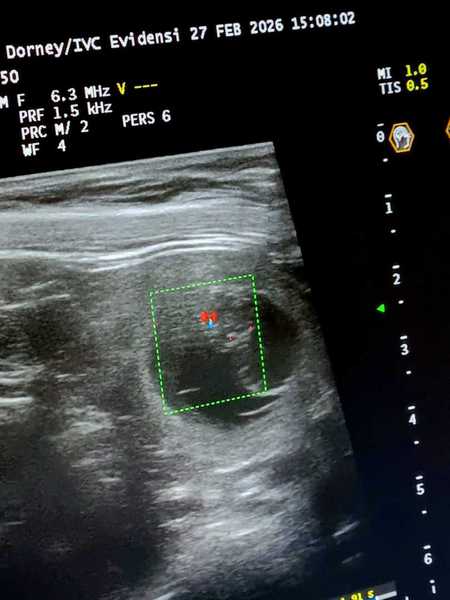

4. Woche     26.Trächtigkeitstag

Heute waren wir zum Ultraschall und was soll ich sagen:

Lani`s Bauch ist voller kleiner Blubberbläschen.

Wir konnten auch schon die kleinen Herzchen schlagen sehen und alles ist für die Zeit bestens entwickelt.